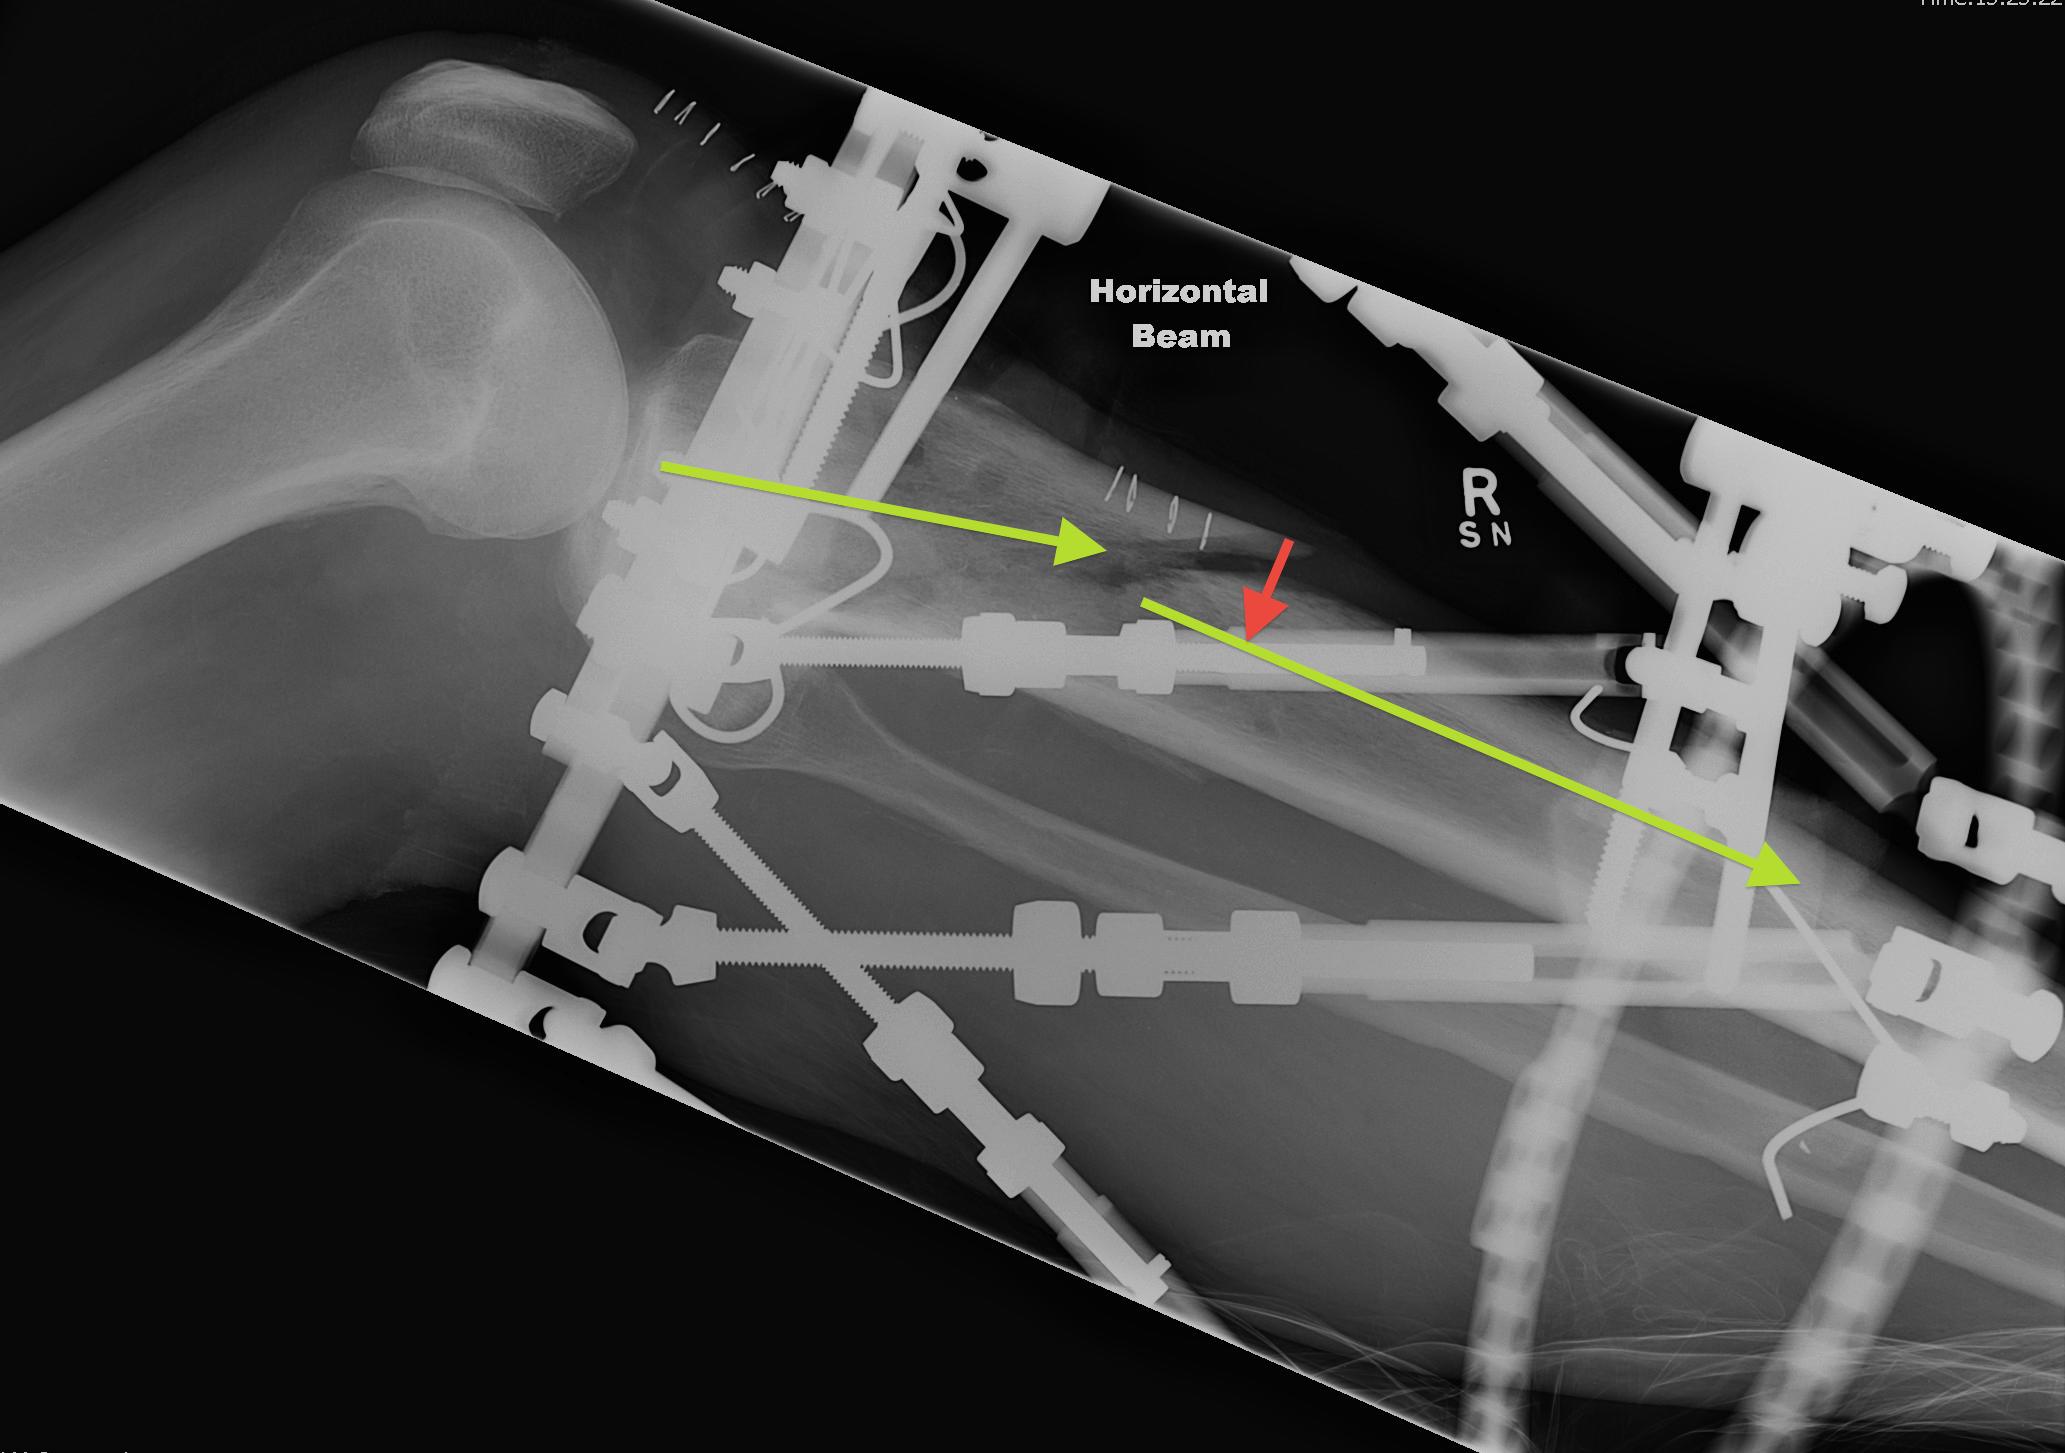

Measure AP and Lateral View Axial Frame Offset

The tibia is not in the centre of the rings

- usually anterior

- need to tell computer where the proximal fragment is in reference to the rings

Estimate Rotatory Offset

If Proximal Ring Tab not centred over anterior border of tibia

- need to clinically estimate the difference

- i.e. 5o